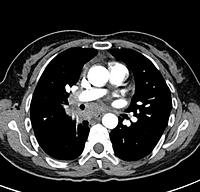

The endobronchial biopsies showed necrotizing granulomas and the cultures were positive for Mycobacterium tuberculosis. The imaging studies show the associated mediastinal and hilar lymphadenopathy.

Lymphadenopathy, TB